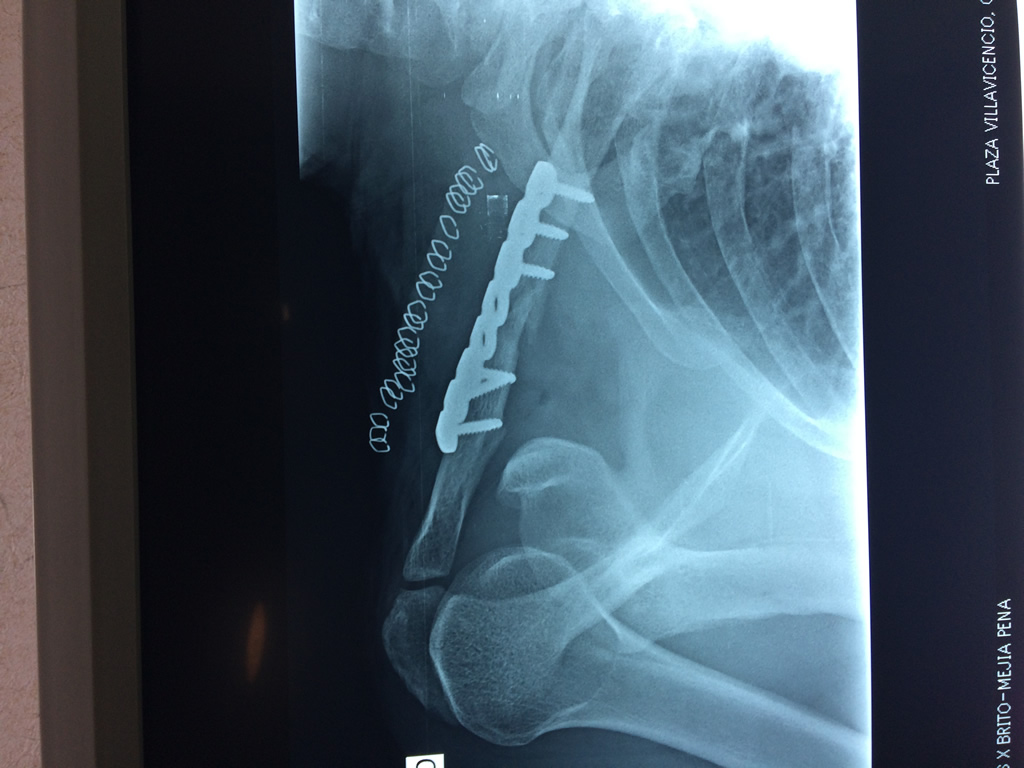

Cirugías de Hombros - Clavícula

La clavícula es un hueso largo, con forma de "S" itálica, situado en la parte anterosuperior del tórax. Junto con la escápula forman la cintura escapular. Se puede palpar por toda su longitud y se extiende del esternón al acromion de la escápula, siguiendo una dirección oblicua lateral y posterior.

Se considera el único medio de unión entre el miembro superior y el tórax. A pesar de su aspecto, similar al de un hueso largo, posee una estructura semejante a la de un hueso plano, ya que carece de epífisis y de diáfisis, lo que la harían entrar dentro de la clasificación de hueso largo. Carece de un canal medular propiamente dicho.